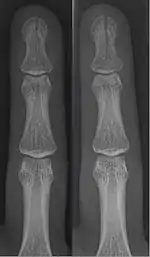

Patterns

| Photo | Type | Description | Causes | Effects |

![]() In the fingertip. More images |

Linear fracture | Parallel to the bone's long axis | ||